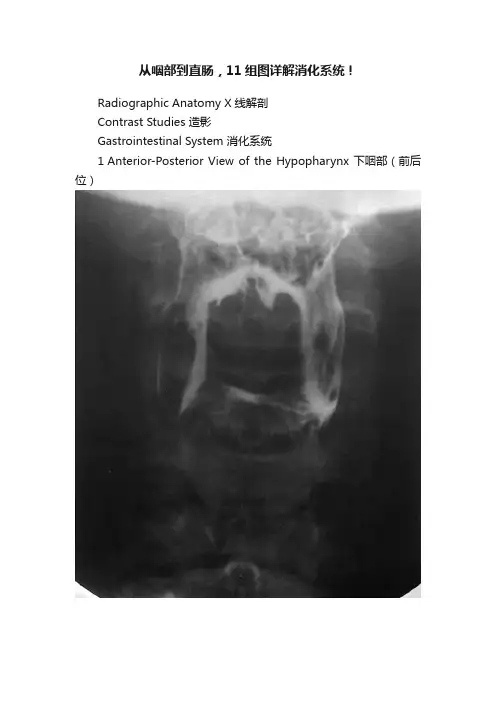

从咽部到直肠,11组图详解消化系统!Radiographic Anatomy X线解剖Contrast Studies 造影Gastrointestinal System 消化系统1 Anterior-Posterior View of the Hypopharynx 下咽部(前后位)1 Pharynx 咽腔,2 Lateral glossoepiglottic fold 舌会厌外侧襞,3 Vallecula 会厌谷,4 Epiglottis 会厌,5 Piriform recess 梨状隐窝,6 Esophagus 食管2 Lateral View of the Hypopharynx 下咽部(侧位)1 Uvula 悬雍垂,2 Cervical spine (axis) 颈椎,3 Tongue 舌,4 Oropharynx 口咽,5 Mandible 下颌骨,6 Vallecula 会厌谷,7 Larynx 喉咽,8 Hyoid bone 舌骨,9 Piriform recess 梨状隐窝,10 Ventricle of the larynx 喉室,11 Esophagus 食管,12 Trachea 气管3 Esophagus 食管1 Uvula 悬雍垂,2 Lateral glossoepiglottic fold 舌会厌外侧襞,3 Epiglottis 会厌,4 Piriform recess 梨状隐窝,5 Upper esophageal sphincter 食管上括约肌,6 Body of the esophagus 食管体部,7 Aortic arch 主动脉弓,8 Bronchial and aortic segment 支气管及主动脉段,A Paratracheal segment 气管旁段,B Aorticsegment 主动脉段,C Bronchial segment 支气管段,D Interbronchial segment 支气管间段,E Retrocardiac segment 心后段,F Epiphrenic segment 膈上段4 Esophagus and Stomach 食管和胃1 Distal esophagus 食管远段,2 Gastroesophageal angle 胃食管角,3 Abdominal esophagus 食管腹段,4 Esophageal hiatus 食管裂孔,5 Cardia 贲门5 Stomach 胃1 Fundus 底,2 Abdominal esophagus 腹段食管,3 Cardia 贲门,4 Lesser curvature 小弯,5 Duodenum 十二指肠,6 duodenal bulb 十二指肠球部,7 Gastric folds (posterior wall) 胃皱襞(后壁),8 Pylorus 幽门,9 Body of the stomach 胃体,10 Angular notch 角切迹,11 Greater curvature 大弯,12 Pyloric antrum 幽门管,12 + 13 Antrum 胃窦6 Stomach and Duodenum 胃和十二指肠1 duodenal bulb 十二指肠球部,2 Pylorus 幽门,3 Pyloric antrum 幽门管(窦),4 Descending duodenum 十二指肠降段,5 Papilla of Vater 十二指肠乳头7 Stomach and Small Bowel 胃和小肠1 duodenal bulb 十二指肠球部,2 Pyloric antrum 幽门窦,3Duodenojejunal flexure 十二指肠空肠曲,4 Colon 结肠,5 Body ofthe stomach 胃体,6 Descending duodenum 十二指肠降段,7 Ascending duodenum 十二指肠升段,8 Horizontal part of duodenum 十二指肠水平段,9 Jejunum 空肠,10 Ileum 回肠8 Small Bowel 小肠1 Jejunum 空肠,2 Junction of the ileum and jejunum 回肠和空肠的连接部,3 Ileum 回肠,4 Cecum 盲肠,5 Appendix 阑尾9 Spot Film of the Ileocecal Region 回盲部(点片)1 Haustra of the colon 结肠袋,2 Ascending colon 升结肠,3 Ileum 回肠,4 Ileocecal valve 回盲瓣,5 Terminal ileum 末端回肠,6 Cecum 盲肠10 Colon 结肠1 Splenic flexure of the colon 结肠脾曲,2 Hepatic flexure of the colon 结肠肝曲,3 Ascending colon 升结肠,4 Transverse colon 横结肠,5 Descending colon 降结肠,6 Haustra 结肠袋,7 Ileocecal valve 回盲瓣,8 Cecum 盲肠,9 Sigmoid colon 乙状结肠,10 Appendix 阑尾,11 Rectum 直肠11 Rectum 直肠1 Rectosigmoid junction 直肠乙状结肠连接部,2 Sacrum 骶骨,3 Retrorectal space 直肠后间隙,4 Transverse rectal fold 直肠横襞,5 Femoral head 股骨头,6 Rectal ampulla 直肠壶腹部,7 Coccyx 尾骨,8 Anorectal junction 肛门直肠交界处系统解剖图授权转载及爆料请联络梅斯医学管理员。